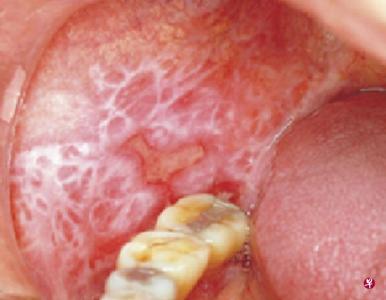

白塞氏病的症状